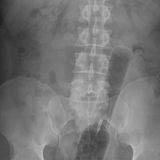

Diese Dinge gehören dort eigentlich nicht hin: Immer wieder passieren Unfälle, wenn Menschen sich zur sexuellen Stimulation über den After Gegenstände in den Darm einführen. Ob Orangen, Spraydosen oder Kaffeebüchsen - der Fantasie sind dabei offenbar keine Grenzen gesetzt.

Die Webseite radiopaedia.org zeigt, welche Dinge Ärzte auf Röntgenbildern schon entdeckt haben. Die Aufnahmen wirken skurril und erschreckend zugleich und machen deutlich, wie weit die eingeführten Dinge bereits in den mescnhlichen Darm vordringen können.

Aber Glück im Unglück für die Patienten: Die Gegenstände können meist ohne Operation entfernt werden. Sehen Sie hier einige der spektakulärsten Röntgenaufnahmen. Da runzeln selbst Chirurgen die Stirn.